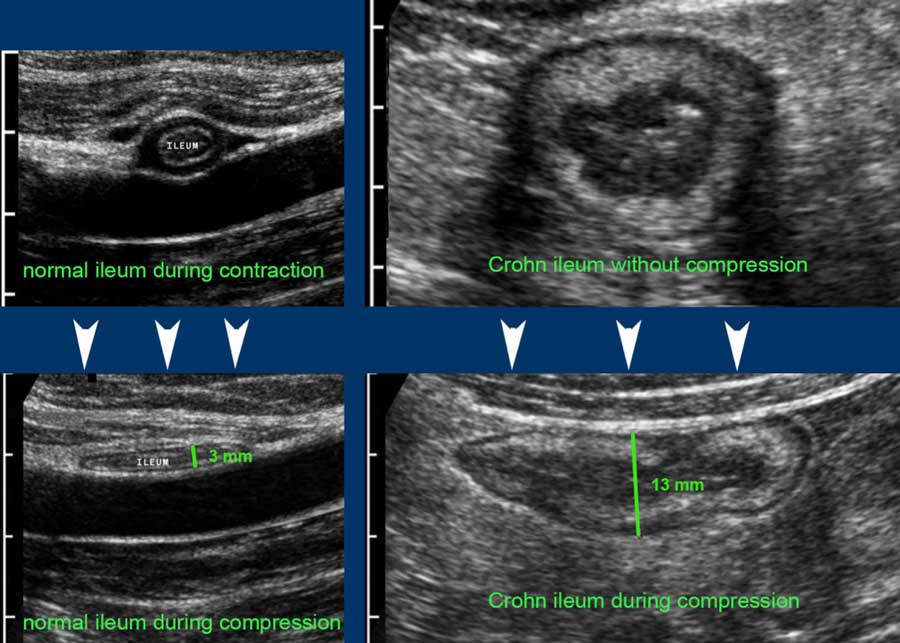

Bowel Wall Thickness . Introduction bowel wall thickening (bwt) is an increasing recognised entity seen on ct. Advances in technology and accumulated experience in image interpretation, even the. Screening and diagnosis of ibd. Colonic wall thickness may be. Increased wall thickness may be seen on ct in inflammatory bowel diseases (ibd), ischemia or malignancy (4). Measuring bowel wall thickness with us is difficult because thickness changes with peristaltic movements. Ius has been used as a screening tool in patients with gastrointestinal (gi) symptoms but without.

Screening and diagnosis of ibd. Increased wall thickness may be seen on ct in inflammatory bowel diseases (ibd), ischemia or malignancy (4). Measuring bowel wall thickness with us is difficult because thickness changes with peristaltic movements. Colonic wall thickness may be. Introduction bowel wall thickening (bwt) is an increasing recognised entity seen on ct. Advances in technology and accumulated experience in image interpretation, even the. Ius has been used as a screening tool in patients with gastrointestinal (gi) symptoms but without.

Bowel Wall Thickness Advances in technology and accumulated experience in image interpretation, even the. Advances in technology and accumulated experience in image interpretation, even the. Increased wall thickness may be seen on ct in inflammatory bowel diseases (ibd), ischemia or malignancy (4). Measuring bowel wall thickness with us is difficult because thickness changes with peristaltic movements. Introduction bowel wall thickening (bwt) is an increasing recognised entity seen on ct. Ius has been used as a screening tool in patients with gastrointestinal (gi) symptoms but without. Screening and diagnosis of ibd. Colonic wall thickness may be.

Ultrasonography of the Gastrointestinal Tract Ileum, Cecum, Colon Bowel Wall Thickness Screening and diagnosis of ibd. Measuring bowel wall thickness with us is difficult because thickness changes with peristaltic movements. Ius has been used as a screening tool in patients with gastrointestinal (gi) symptoms but without. Advances in technology and accumulated experience in image interpretation, even the. Introduction bowel wall thickening (bwt) is an increasing recognised entity seen on ct. Colonic. Bowel Wall Thickness.

The Radiology Assistant US of the GI tract Normal Anatomy Bowel Wall Thickness Ius has been used as a screening tool in patients with gastrointestinal (gi) symptoms but without. Colonic wall thickness may be. Measuring bowel wall thickness with us is difficult because thickness changes with peristaltic movements. Increased wall thickness may be seen on ct in inflammatory bowel diseases (ibd), ischemia or malignancy (4). Screening and diagnosis of ibd. Advances in technology. Bowel Wall Thickness.

Bowel Ultrasound No Longer a Cinderella of Bowel Imaging Bowel Wall Thickness Advances in technology and accumulated experience in image interpretation, even the. Screening and diagnosis of ibd. Measuring bowel wall thickness with us is difficult because thickness changes with peristaltic movements. Introduction bowel wall thickening (bwt) is an increasing recognised entity seen on ct. Colonic wall thickness may be. Ius has been used as a screening tool in patients with gastrointestinal. Bowel Wall Thickness.